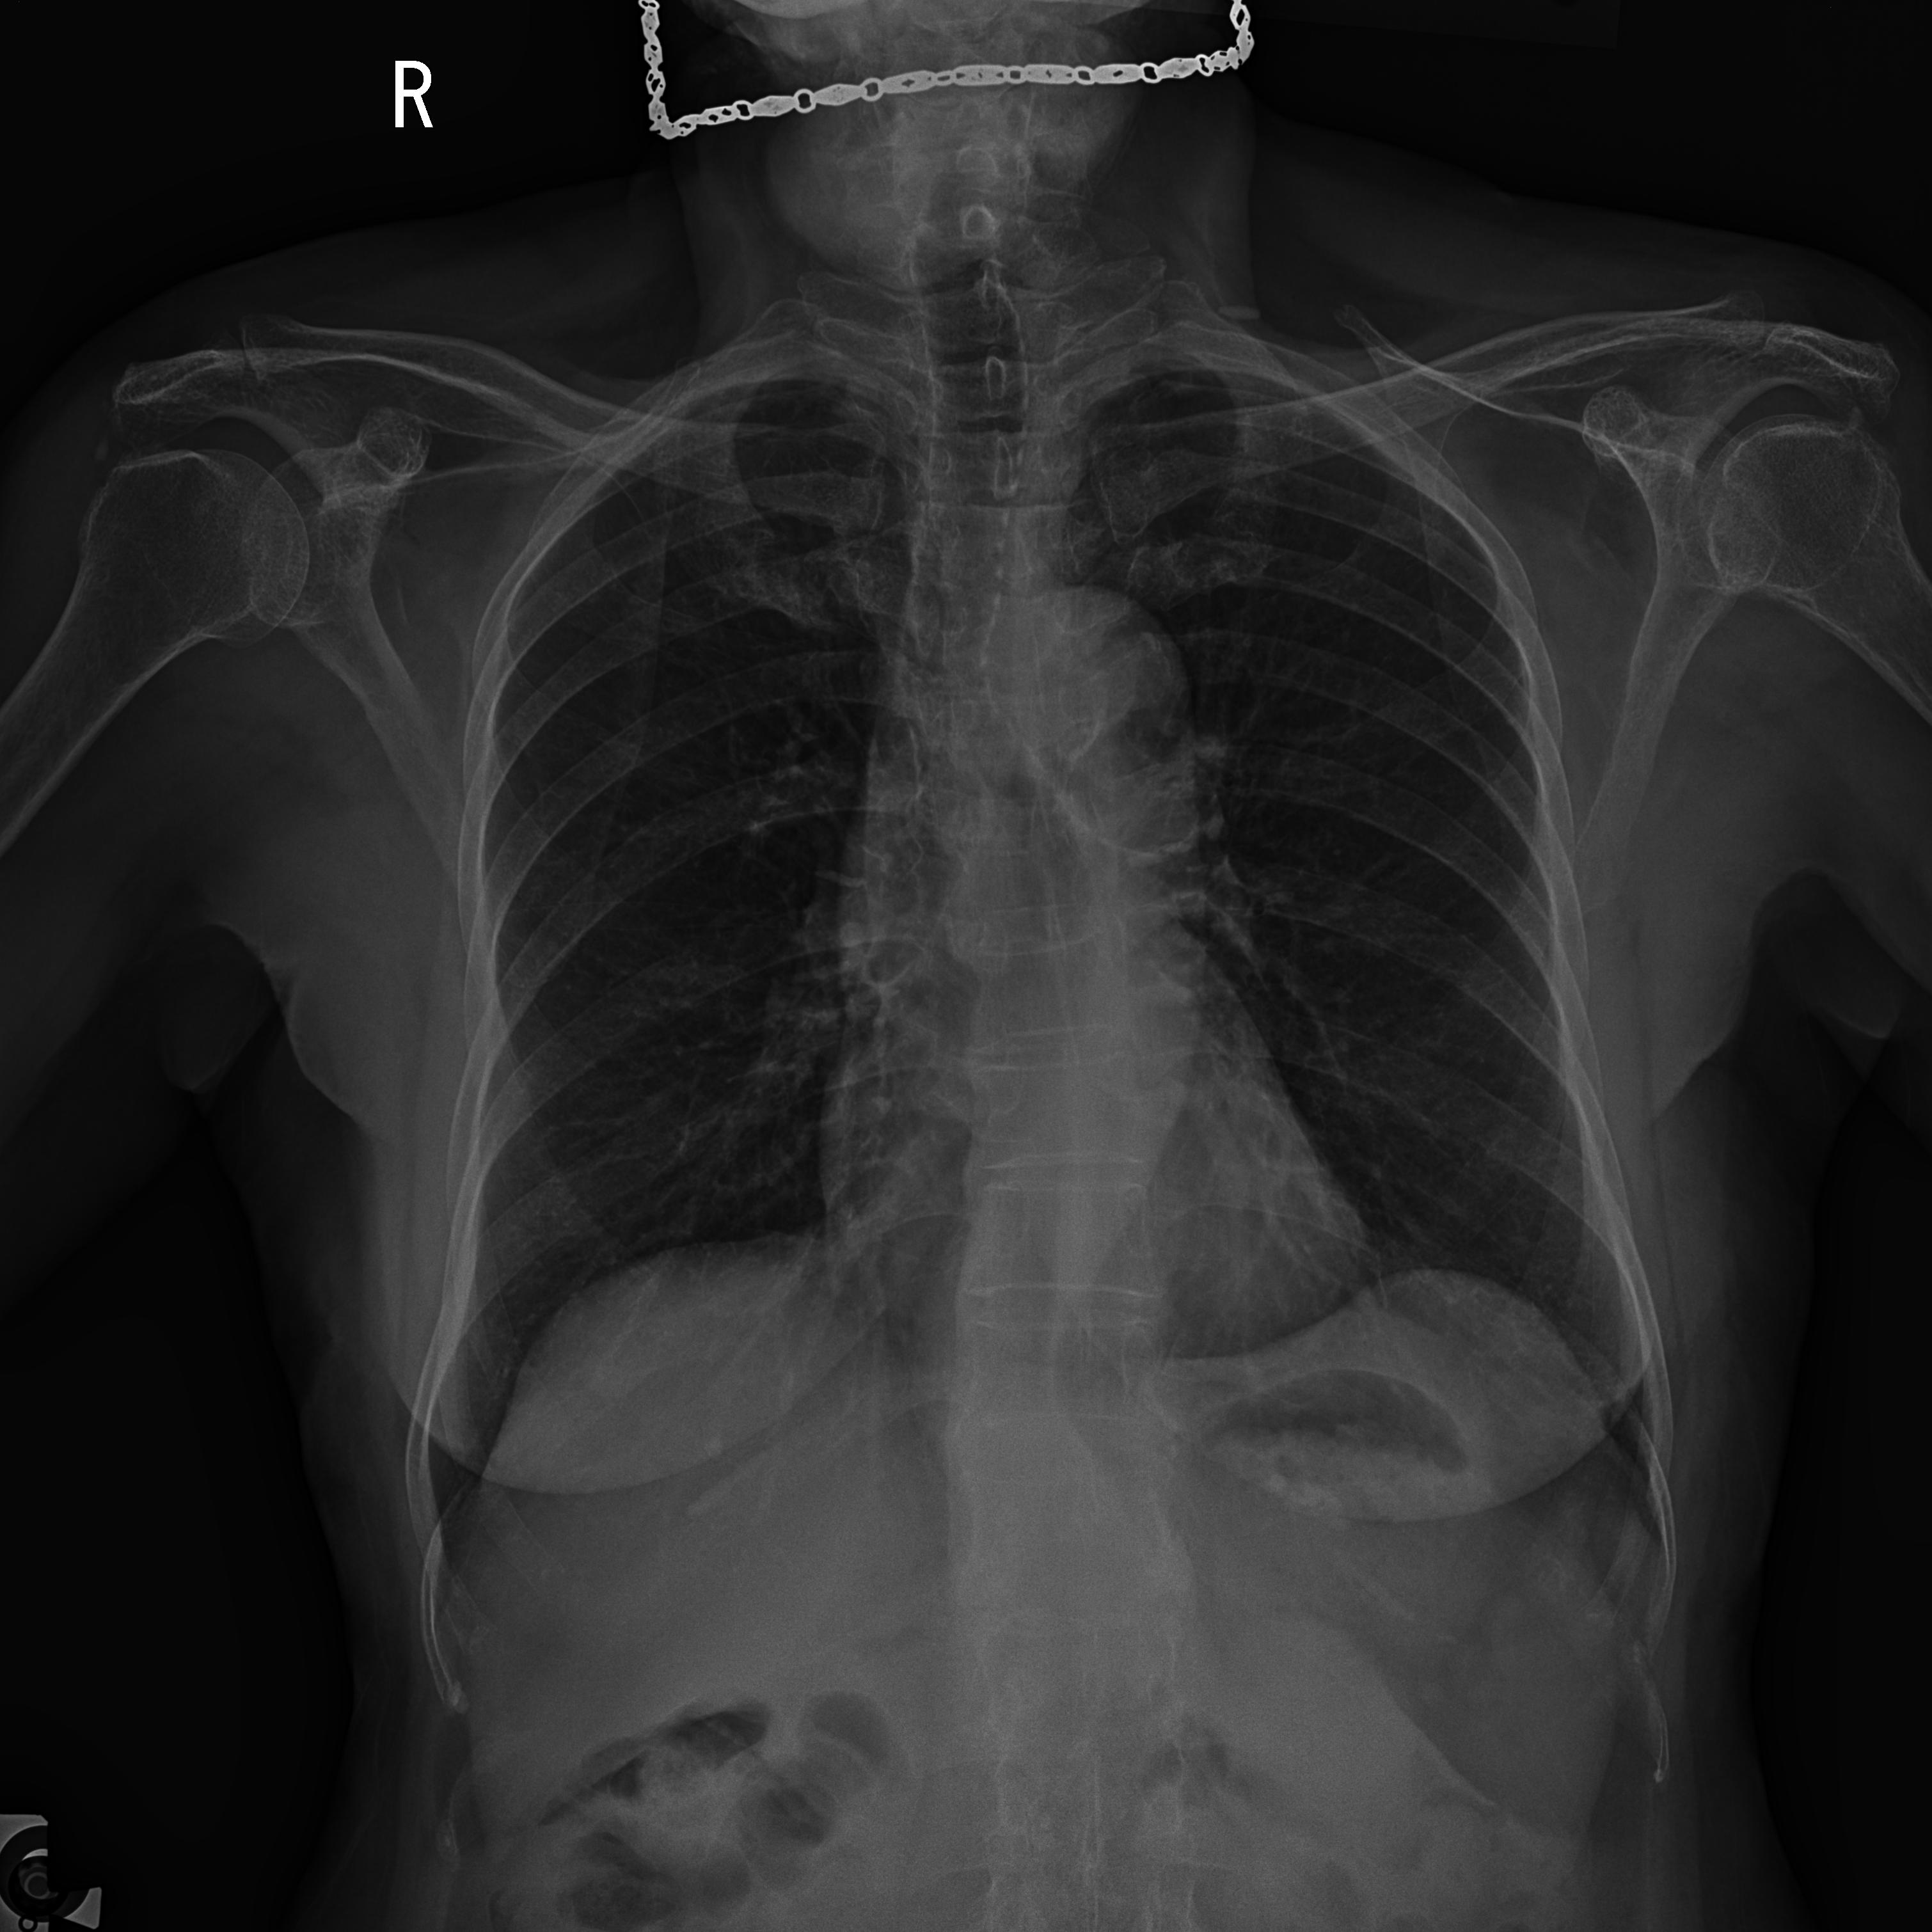

We provide patient information, including gender, age, and the X-ray view type, along with the X-ray image of the patient. An example of the input used in Stage 1 - findings generation is illustrated in Table 7.

Stage 1 - Findings Generation "Role": "System" - "Content": "Bạn là trợ lý bác sĩ (You are a medical assistant)"

"Role": "User" - "Content": "Ảnh chụp X-ray PA (Chụp Xquang tim phổi thẳng) bệnh nhân nam, 72 tuổi. Cho biết bệnh nhân bị gì?" ((X-ray PA image (Posteroanterior chest X-ray) of a 72-year-old male patient. Please indicate what condition the patient has))

"Role": "User" - "Content":

[Uncaptioned image]

"Ground Truth": "Phổi hai bên kém sáng, mờ kính rải rác, rốn phổi tăng đậm nhẹ. Bờ vòm hoành hai bên đều, hai góc sườn hoành nhọn. Bóng mờ tim không to. Vôi hóa thành quai động mạch chủ." (The lungs are bilaterally hypolucent with scattered ground-glass opacities. Mild hilar prominence is noted. The diaphragmatic contours are smooth, and both costophrenic angles are sharp. The cardiac silhouette is within normal limits. Calcifications are seen in the wall of the aortic arch.)

Table 7: An example of Stage 1 input for findings generation